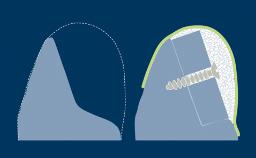

The esthetic aspects of implant prostheses have gained increasing attention and importance in recent years. There are a number of factors that determine if implant prostheses are considered esthetically successful by both the patient and the clinician.

With the aim of achieving optimal esthetics, this Learning Module will outline and discuss the determining factors related to esthetic planning for fixed dental prostheses or FDPs.

- describe prosthesis-related factors that guide planning of esthetic implant-supported FDPs

- describe peri-implant soft tissue factors that guide planning of esthetic implant-supported FDPs